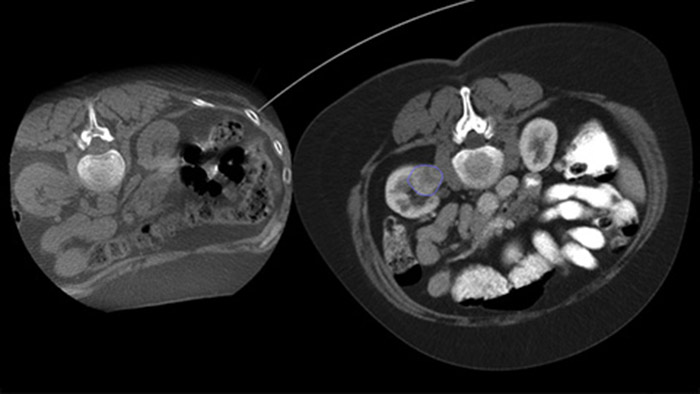

Dual Viewでは、手技中3D CBCT Dual上に術前3D画像(CT/MR/PET-CT)をオーバーレイして、病変の視認性を高め、ニードル計画に必要な重要情報にアクセスできます。

CBCTを使用すると、アブレーション後CBCTを収集して腫瘍対象範囲を示し、治療の結果を確認できます。